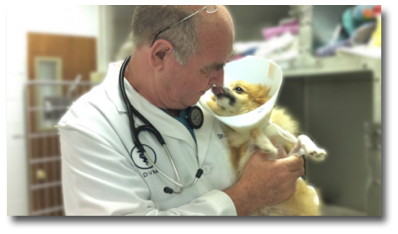

At Kahala Pet Hospital, we know how important and precious your pets are to you. We embrace that relationship and truly consider each of them part of our practice family too. We strive to provide the best, most complete care for your pet from puppy and kitten, and on into the senior years.

Dr. Patrick Leadbeater, and our team of veterinary medical professionals would love to meet you and your pets. Prior to beginning any exam, we spend time bonding with your pet . This provides a level of comfort and confidence that other veterinary hospitals may overlook. Whether your pet is due for a routine veterinary exam, or is in need of treatment for a joint or back problem, heart condition or even cancer, we're here to serve you.

Dr. Patrick Leadbeater, and his team, build a special rapport with your pets. We take the time to stroke and talk to your pet before we ever begin an exam. We build a trust with each animal, making exams far less stressful for your pet and for you. Many pets come through the door wagging their tails, and eager to greet any of our staff that they meet.